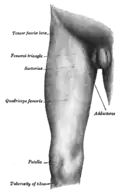

Quadriceps femoris, with different muscles in different colors.

The quadriceps femoris muscle (/ˈkwɒdrɪsɛps ˈfɛmərɪs/, also called the quadriceps extensor, quadriceps or quads) is a large muscle group that includes the four prevailing muscles on the front of the thigh. It is the sole extensor muscle of the knee, forming a large fleshy mass which covers the front and sides of the femur. The name derives from Latin four-headed muscle of the femur.

The quadriceps femoris muscle is subdivided into four separate muscles (the 'heads'),[1][2] with the first superficial to the other three over the femur (from the trochanters to the condyles):

- The rectus femoris muscle occupies the middle of the thigh, covering most of the other three quadriceps muscles.[1] It originates on the ilium. It is named for its straight course.

- The vastus lateralis muscle is on the lateral side of the femur (i.e., on the outer side of the thigh).[1]

- The vastus medialis muscle is on the medial side of the femur (i.e., on the inner side of the thigh).[1]

- The vastus intermedius muscle lies between vastus lateralis and vastus medialis on the front of the femur (i.e., on the top or front of the thigh), but deep to the rectus femoris muscle. Typically, it cannot be seen without dissection of the rectus femoris.[1]